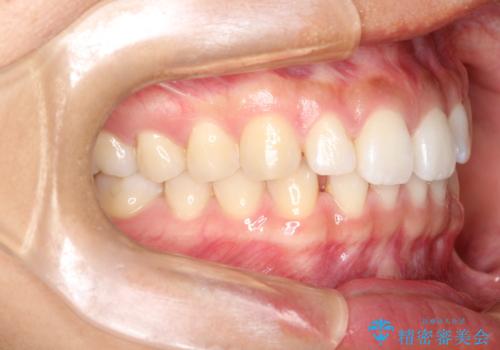

すきっ歯のインビザラインによる目立たない矯正

- すきっ歯を治したいとのことで来院されました。

上下ともに前歯に隙間がありました。

目立たない装置をご希望のためインビザラインで矯正治療を行うこととしました。

使用時間を守っていただけたので、スムーズに治療を終わることができました。